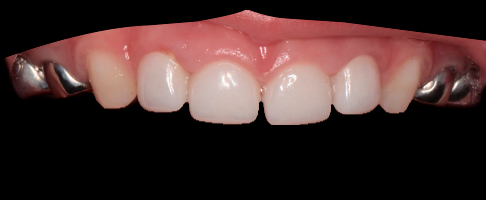

- восстановление фронтальной группы молочных зубов эстетическими циркониевыми коронками.